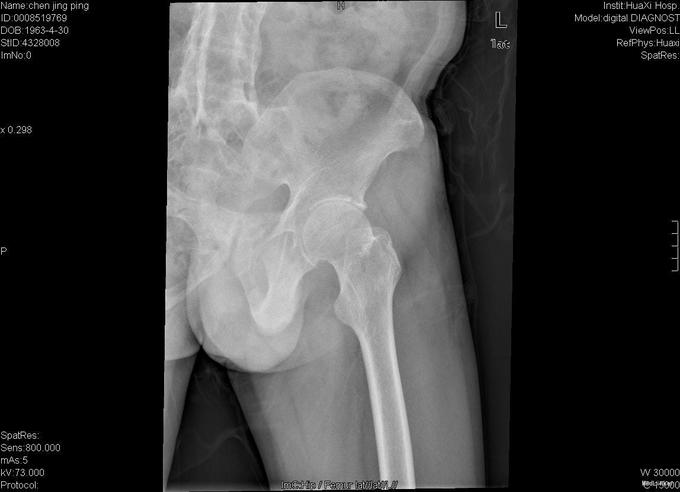

查体:跛行步态,强迫体位,脊柱强直后凸畸形,活动受限。右髋强直畸形,压痛、叩痛,无瘢痕、窦道,无皮损、皮癣,活动受限。双下肢感觉无明显异常。 辅助检查:x线片:脊柱呈"竹节样"改变,腰椎小关节间隙模糊,双侧骶髂关节及右髋关节间隙消失,骨性融合。

诊断:强直性脊柱炎 右髋关节强直 治疗:完善相关检查后在全麻下行右侧全髋关节置换术+髋臼成形术,手术顺利,术后予以抗炎+抗凝+阵痛等治疗。

术后患者恢复良好,右髋屈曲100°,伸直0°,外展40° 1、强直性脊柱炎起病特点有哪些 2、实验室检查及影像学表现有何特点? 3、治疗原则及主要治疗方法有哪些?